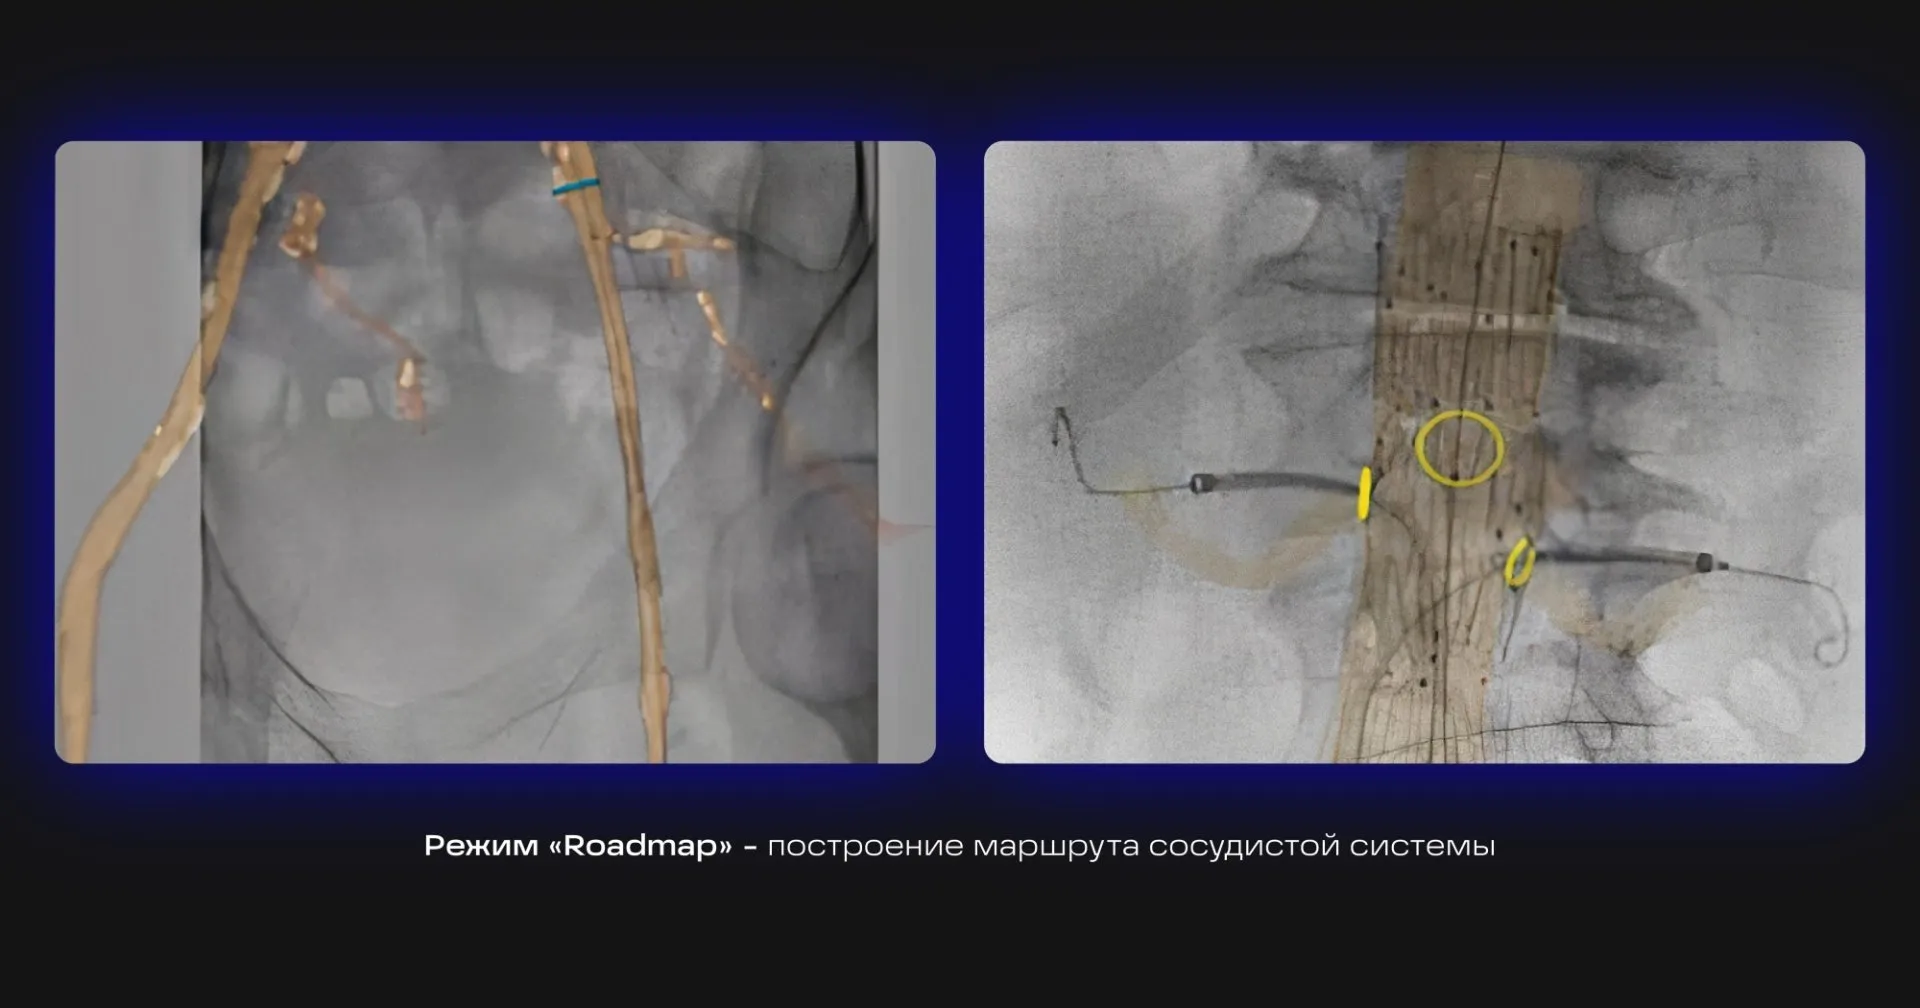

Режим «Roadmap» — построение маршрута сосудистой системы на «живом» изображении в реальном времени для навигации проводника.